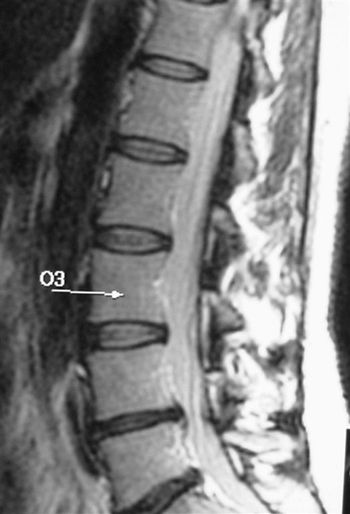

Results of a study by Greek researchers suggest that percutaneous disc decompression, a newly developed outpatient procedure for herniated vertebral discs, has better long-term effects than conservative therapy.

Results of a study by Greek researchers suggest that percutaneous disc decompression, a newly developed outpatient procedure for herniated vertebral discs, has better long-term effects than conservative therapy. They released findings Wednesday at the 2009 RSNA meeting.